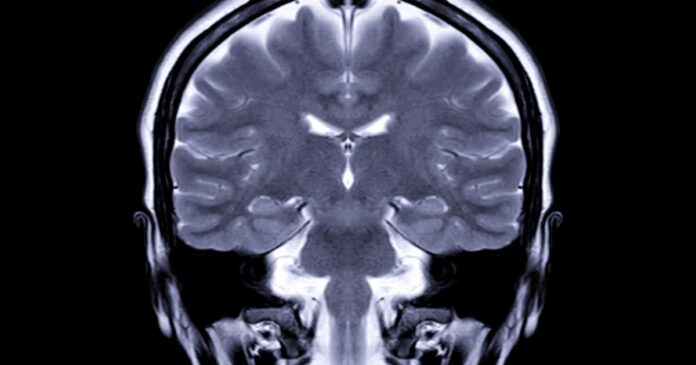

Combinando ressonância magnética e inteligência artificial, os cientistas identificaram que o álcool pode antecipar danos neurais que normalmente só apareceriam décadas depois, levantando um sinal de alerta especialmente para jovens que iniciaram o hábito ainda na adolescência.

A pesquisa avaliou 58 adultos com idades entre 22 e 40 anos, a maioria com histórico de consumo alcoólico desde a juventude. Após responderem a questionários sobre hábitos de bebida, os participantes foram submetidos a testes de flexibilidade cognitiva e exames de ressonância magnética em 3D.

A partir das imagens cerebrais, algoritmos de machine learning calcularam a chamada Diferença de Idade Predita (DAP), uma métrica que estima o quanto o cérebro aparenta ser mais velho do que a idade real da pessoa. Quanto maior o consumo de álcool, maior foi a discrepância — ou seja, maior o envelhecimento cerebral.